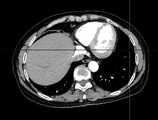

Fig. 8a is a schematic diagram of a sequence of CT images viewed from a transverse direction.

fig. 8a-8c are raw three-dimensional data of sequential CT images viewed from three directions, the transverse, sagittal and coronal planes, respectively. Fig. 9a to 9c are the second binarized images obtained after the method removes the bed plate area, respectively, and it can be seen from fig. 9a to 9c that none of the skin surface contours of the human body area is damaged. Fig. 10a to 10c are respectively third binarized images obtained after filling the cavity by the method, and it can be seen from fig. 10a to 10c that the third binarized images are completely overlapped with the original three-dimensional data of the sequence CT image, and the lung region with a low threshold value is effectively filled. As can be seen from FIGS. 11a-11d, after another serial CT image is reconstructed by the method, the three-dimensional model of the skin can be fused with the third binary image and the serial CT image. And finally mapping the obtained three-dimensional model of the skin back to a 2D mode, and comparing the coincidence degree of the skin boundary in the three-dimensional model of the skin and the binary image to obtain figures 12a-12 c. In addition, the three-dimensional models of the skin of other parts of the human body obtained by the method are shown in figures 13a-13 c.